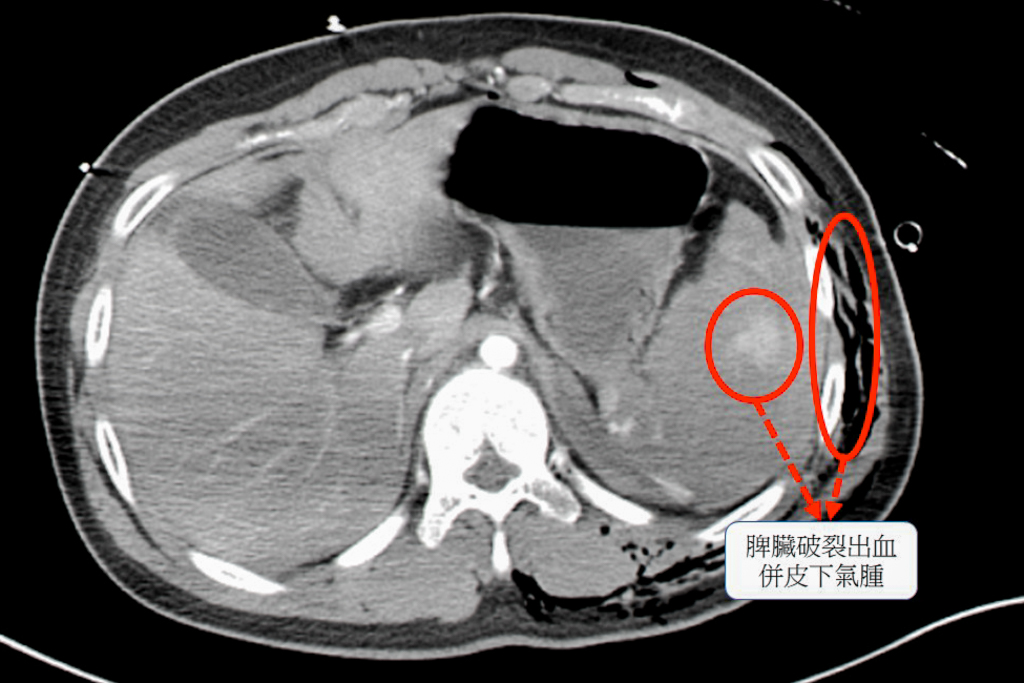

經過電腦斷層檢查,確認患者的脾臟已完全碎裂,是體內大出血的主因 ,同時合併胸腔積血、積氣,以及多處骨折與血管撕裂傷 。面對如此複雜的傷勢,外科團隊首先進行緊急手術,切除破裂的脾臟以控制出血 ;骨科與整形外科團隊則接力進行骨折固定與血管修補,成功穩定了患者的生命跡象 。

經過電腦斷層檢查,確認患者的脾臟已完全碎裂,是體內大出血的主因 ,同時合併胸腔積血、積氣,以及多處骨折與血管撕裂傷 。